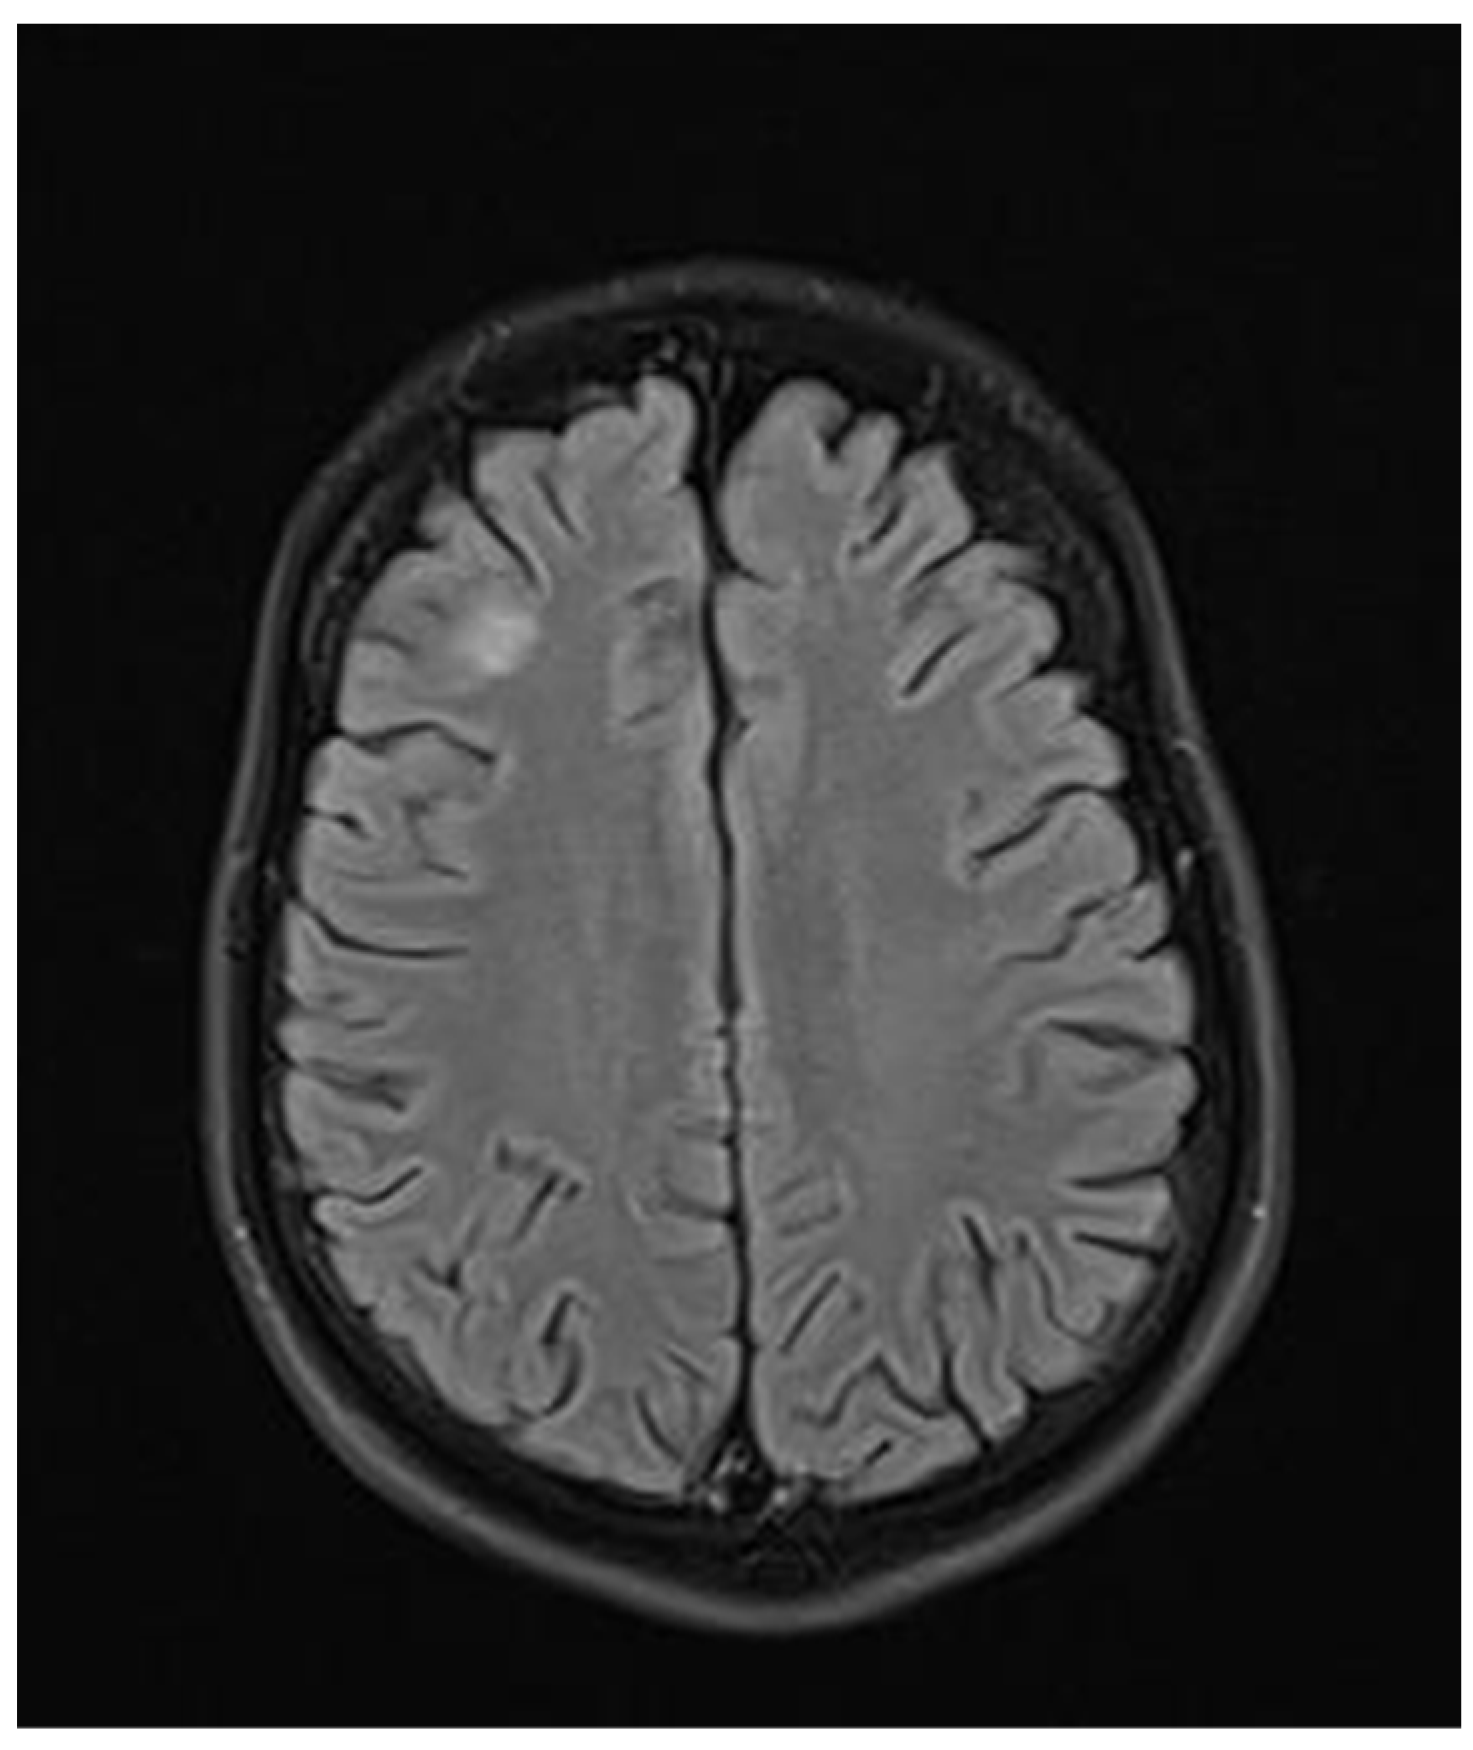

Figure 3.

Transverse FLAIR brain magnetic resonance image showing numerous foci of increased signal between the basal nuclei (December 2021).

During hospitalization in the neurology ward, Holter EEG was performed in which seizure episodes corresponded to changes in the recording. Interictal EEG showed rapid activity followed by slow theta waves and several sharp and slow wave complexes (Figure 1 and Figure 2). Topiramate was added to valproic acid at a target dose of 2 mg/kg of body weight. Gradual seizure relief was observed in the following weeks, and there were no other neurological manifestations for another nine months. After that time, in December 2021, the patient was admitted to the pediatric ward due to impaired consciousness and persistent vomiting, followed by paresis of the lower limbs. A brain MRI was performed, which showed “T2/FLAIR images reveal poorly defined areas of increased signal in the brain’s white matter, both above and below the tentorium, as well as in the periventricular and subcortical regions. These areas correspond to low signal regions in T1 images. The largest change area measures 19 × 14 mm and is located in the right middle cerebellar peduncle, which merges with changes observed in the pons. Additionally, there is a lesion in the right thalamus, measuring 10 × 24 mm, along with numerous scattered foci in the corona radiata and between the basal nuclei. Overall, the imaging findings primarily suggest acute disseminated encephalomyelitis (ADEM)” (Figure 3 and Figure 4). Cerebrospinal fluid examination revealed oligoclonal bands and an elevated protein level of 118.5 mg/dL (reference range: 15.0–45.0 mg/dL) and a slightly elevated leukocyte level of 29/mm3 (lymphocytes 72.4%, neutrophils 27.6%).